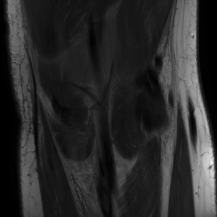

| Ground Truth | LORAKI | Global | LONDN-MRI | LONDN-MRI | Oracle |

| (1 iteration) | (2 iterations) | ||||

![]() |

| PSNR = dB | PSNR = 31.45 dB | PSNR = 32.15 dB | PSNR = 32.72 dB | PSNR = 33.15 dB | PSNR = 33.22 dB |